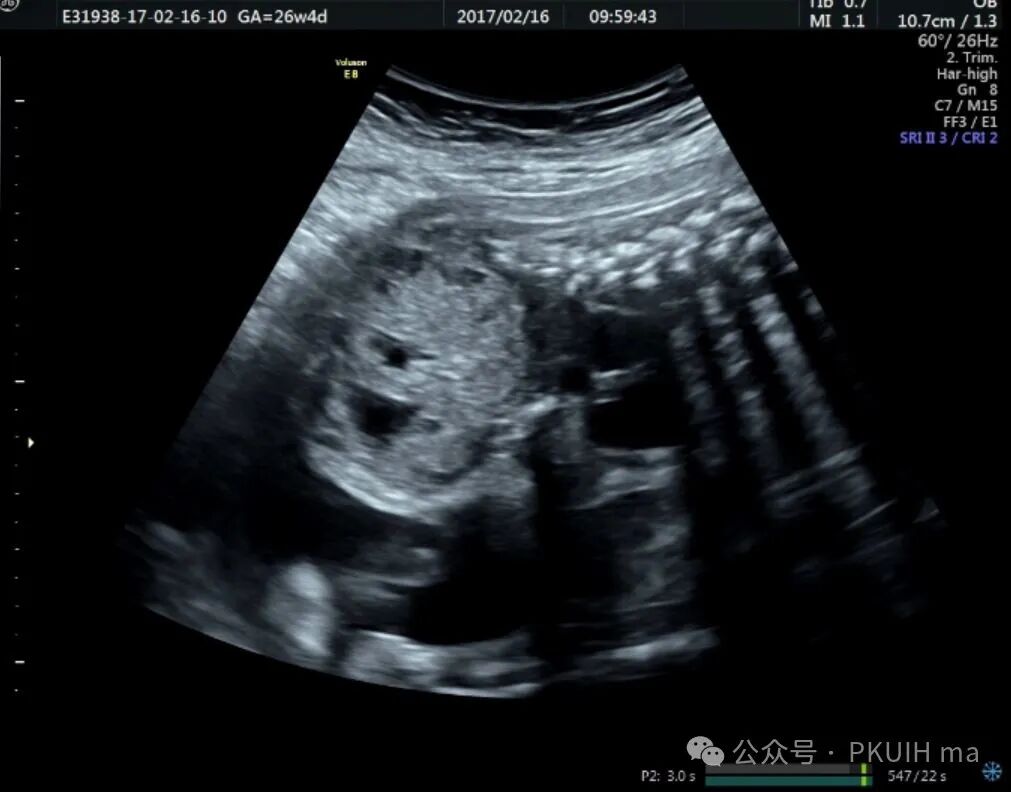

上图是22周系统排畸发现的骶尾部畸胎瘤,随访中发现肿瘤生长过快并血流相对丰富,最后选择了放弃